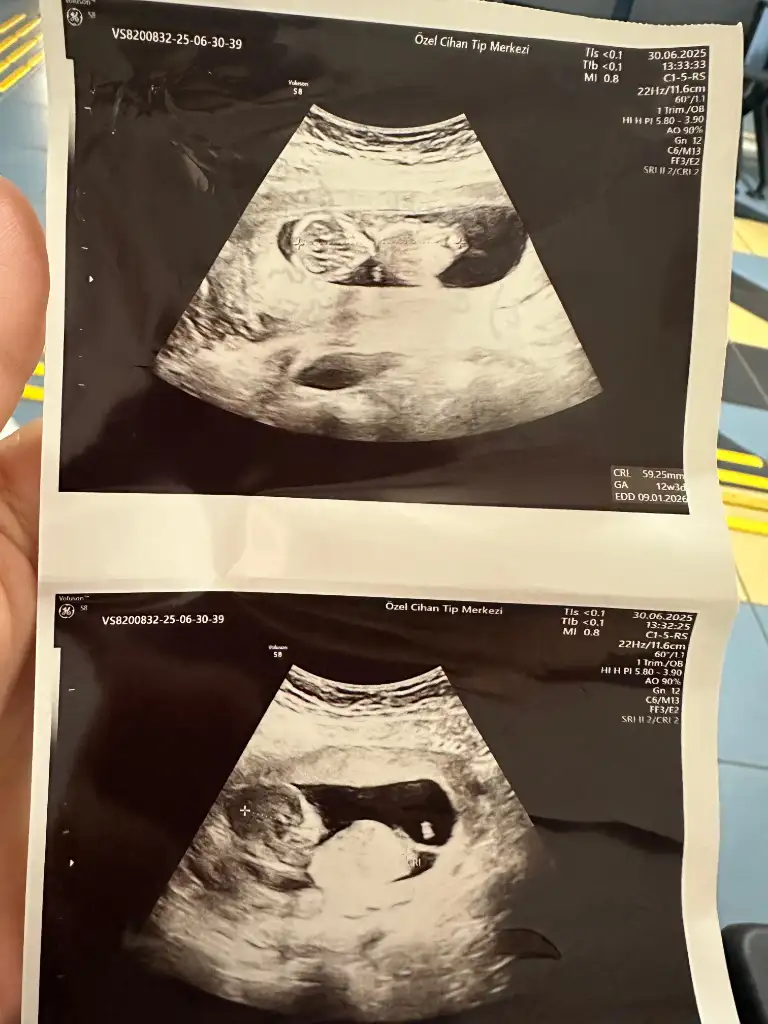

Bu resime göre 14 hafta bi kız dediler bi erkek sizce bu resimde cinsiyet nub teorisi olarak nedir?Normalde belli olması lazım

14 haftalıklı videoda net gözüküyorda ben bunu yakalayabildim sizinkindede arada böyle bir çıkıntı gözüküyorsa erkektirAnladım sizinki de çok bariz değil galiba büyük göstermiyor kac hafta

Belkide olabilir farklı pozisyonlardan bakınca doktor belli oluyorda bu gittiğinizde netleşir ilk çocuğunuzmuZaten benim 13+1 belki de görünmedi daha kasigi kapatiyormus